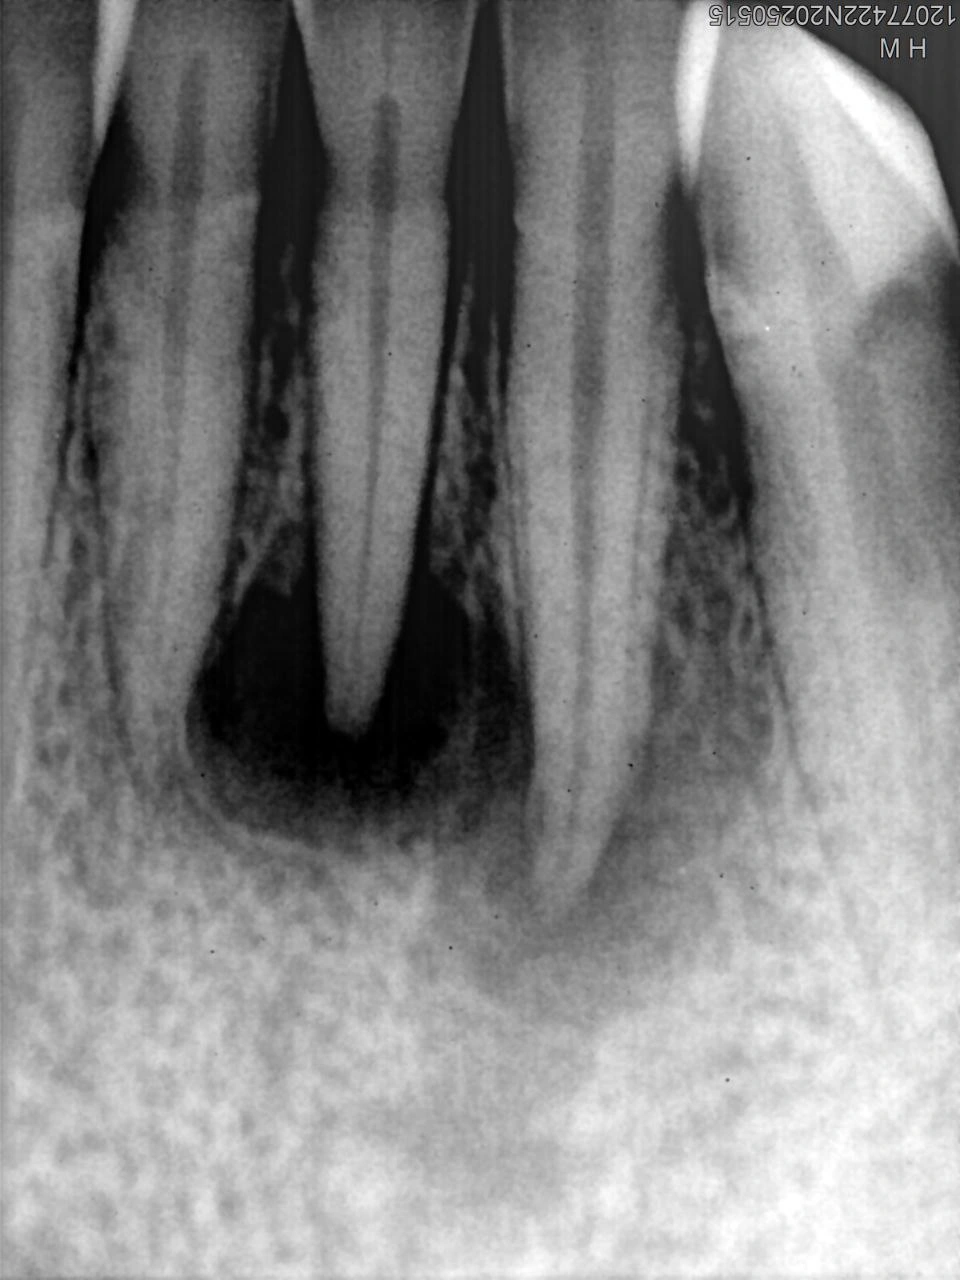

Clinical Cases